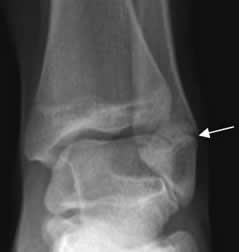

Fig 71. Salter tipo I.

Rx AP. Esclerosis e irregularidad en las placas de crecimiento del peroné, por cicatrización de lesión Salter tipo I.